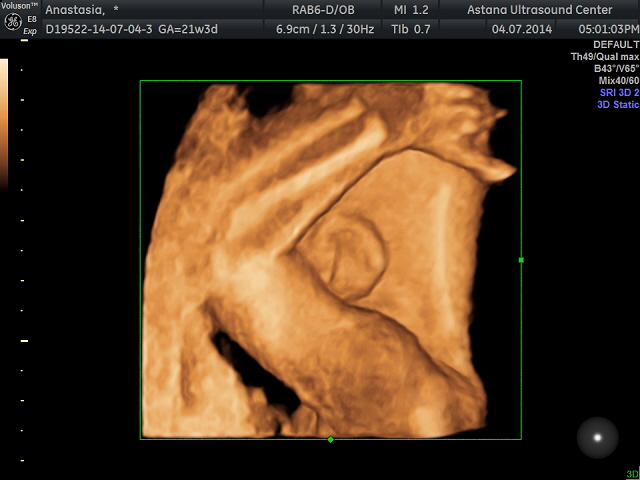

вот наше ушко все отлично не каких поталогий ребенок здоровый! я такая счастливая! спасибо всем за поддержку